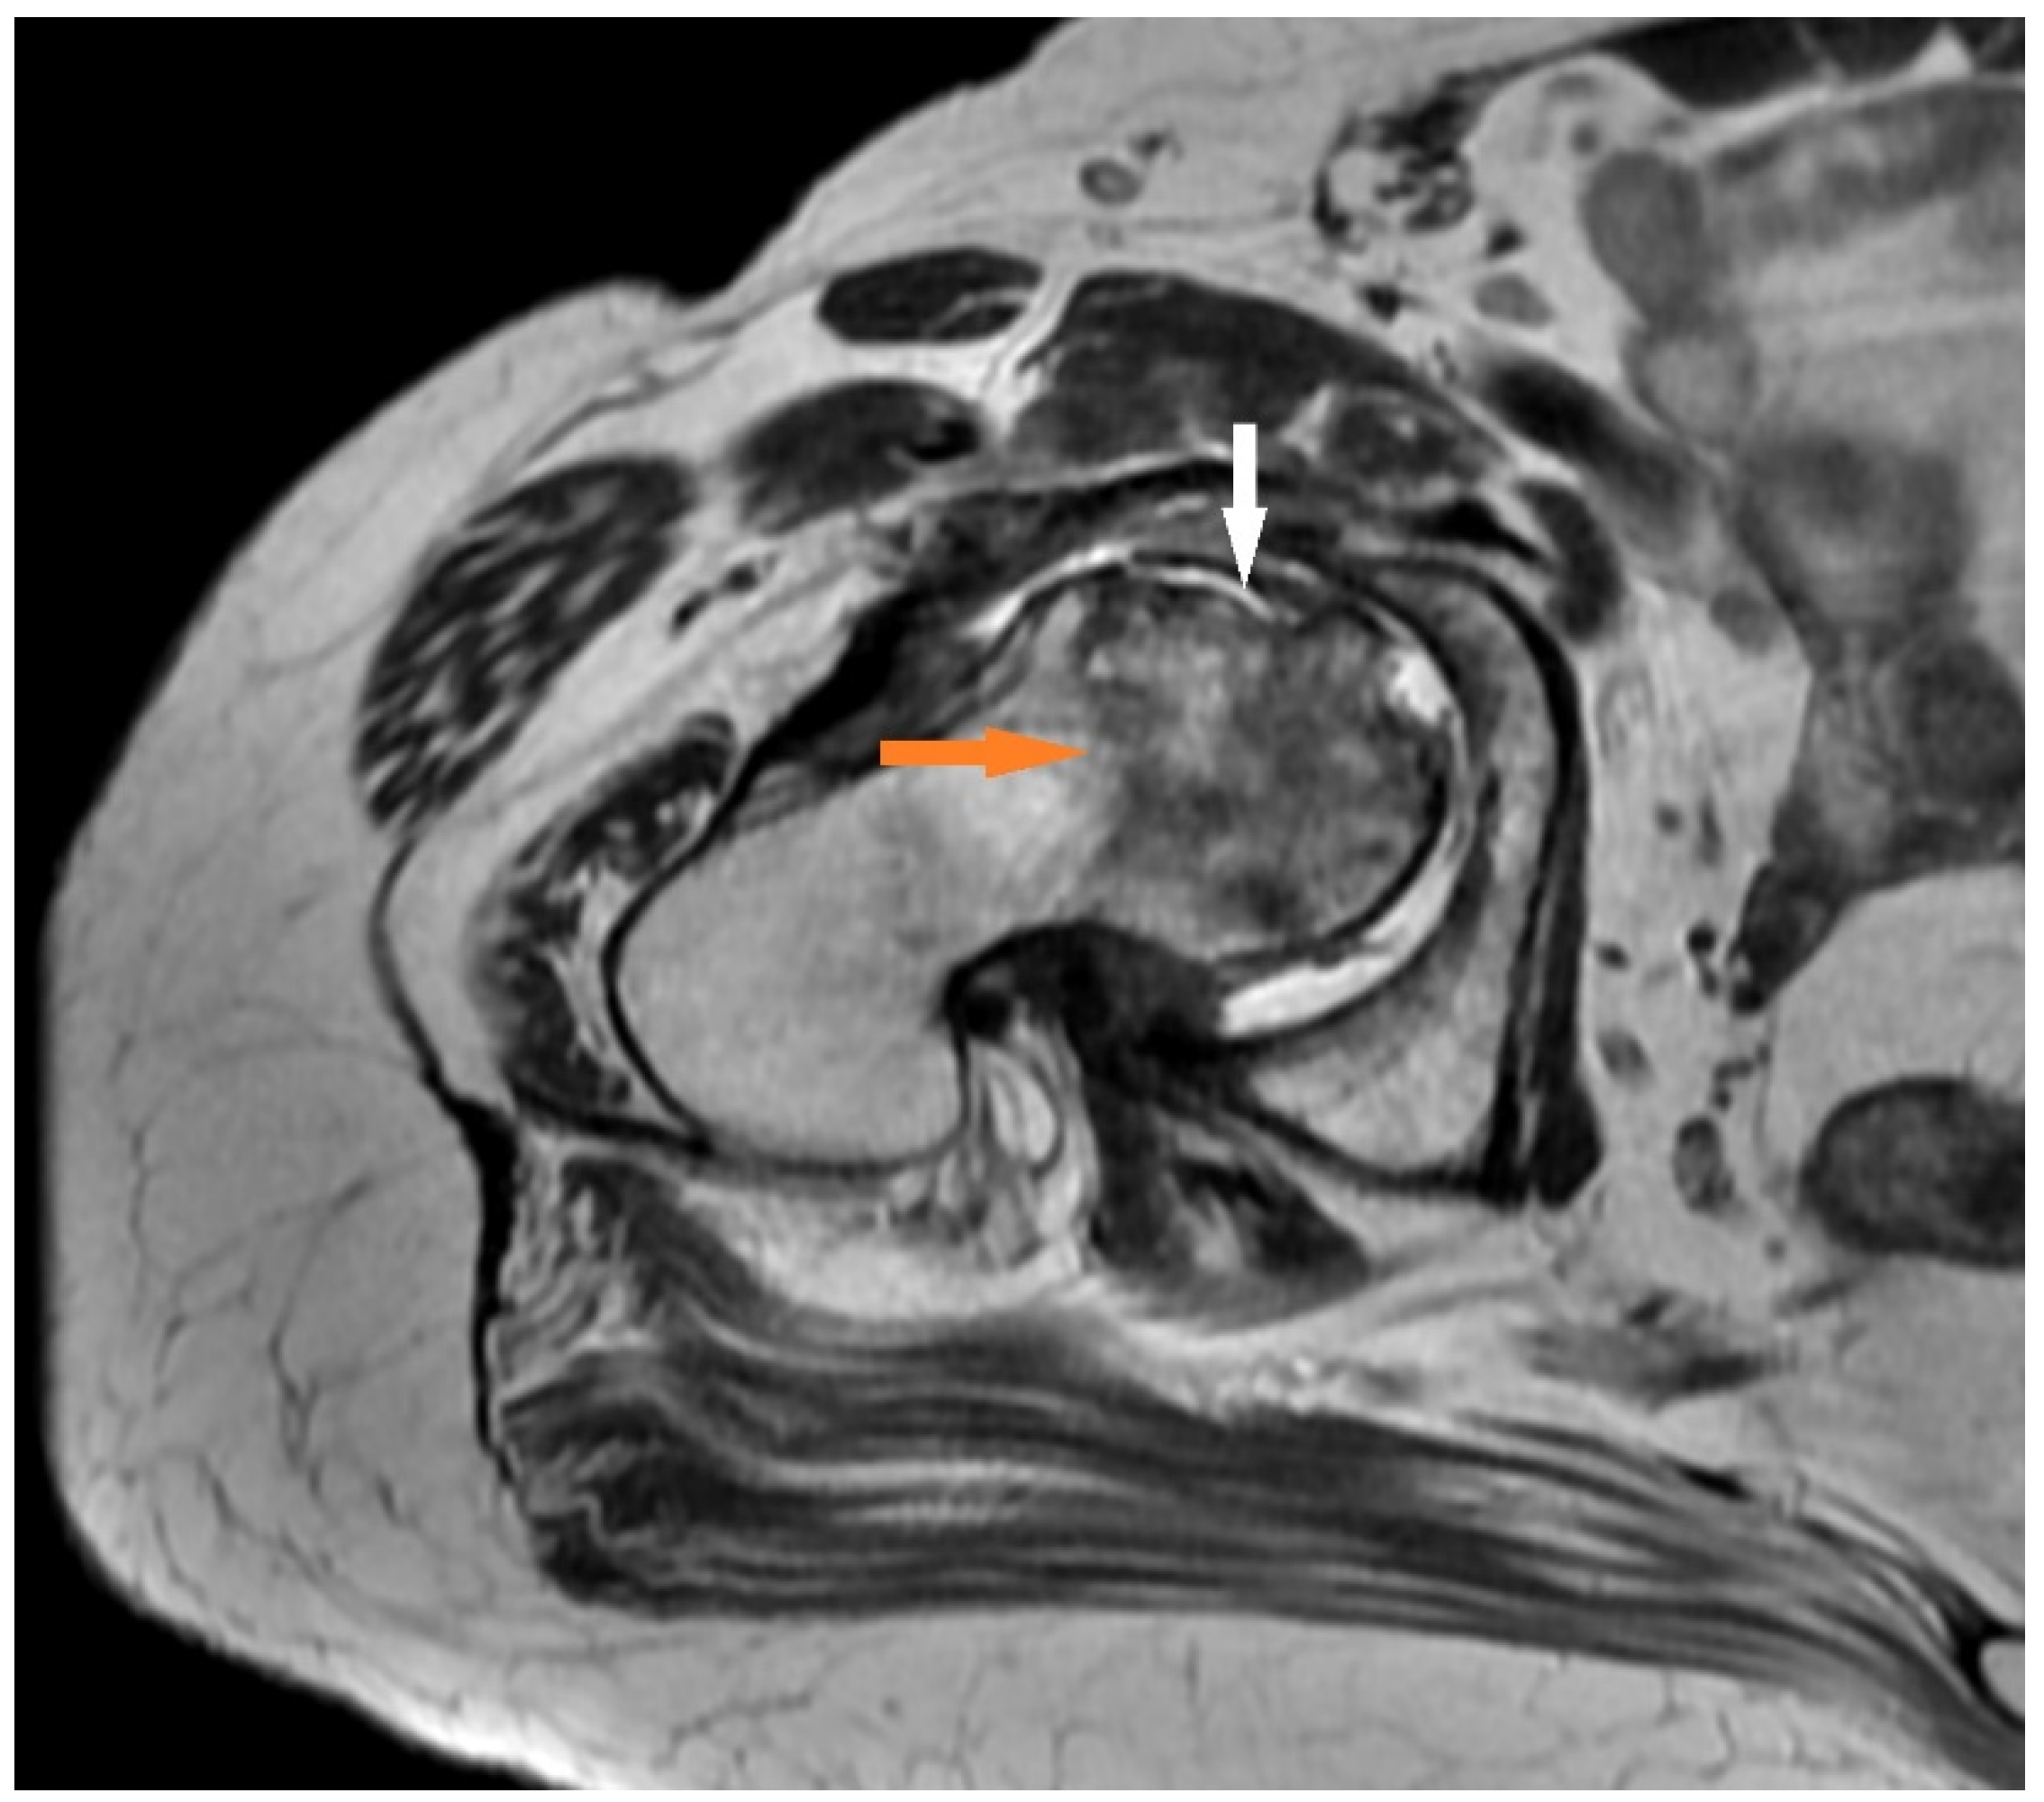

3.1.2. Case 2 (Patient No. 1)

| 1 | hip | 11 | yes | 4 | 10 | 8 | 2 |